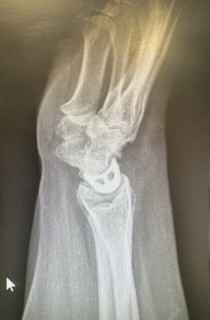

X-rays and MRIs can be used to ensure the correct location, where an X-ray will show a widening of the scapholunate gap and/or a ‘ring sign’ on the scaphoid.

The pain felt after a scaphoid fracture can often be mistaken for a scapholunate ligament sprain as the pain isn’t typically as bad as other wrist fractures. As with all fractures, an X-ray will determine a breakage, however, scaphoid fractures can be difficult to identify due to the other carpal bones hiding the scaphoid.

In some cases, an MRI or CT scan might be needed in place to accurately diagnose the injury.